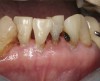

Fig 6. Use of 38% SDF to arrest root caries in permanent teeth of an elderly patient. Fig 6: The arrested root carious lesions were hard to probe.

Figure 6